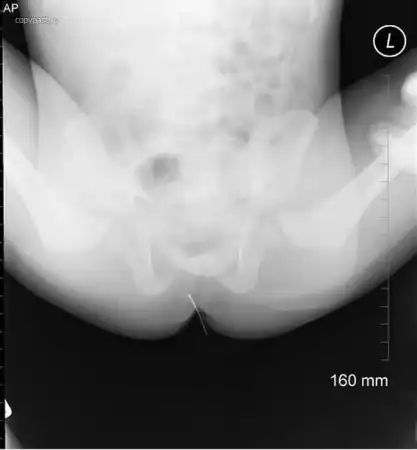

Маленький ребенок проглотил иголку. Она прошла через весь желудок и вышла там,

где и должна была.

Родители только тогда ее и заметили, и отвезли малыша в больницу